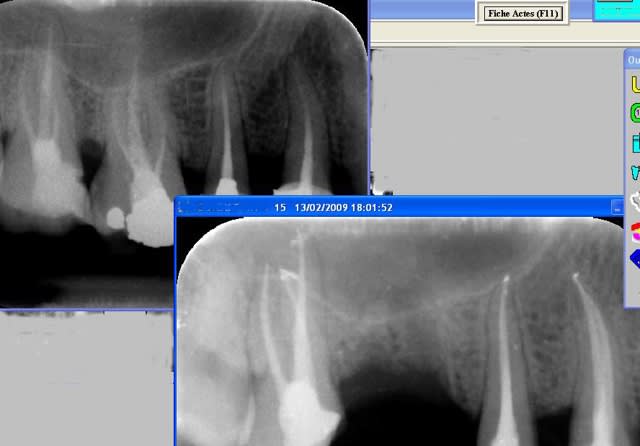

15/02/2009 à 17h52

Bonsoir les Confrères,

La littérature décrit depuis longtemps :"...le compactage à chaud de gutta percha semble être la technique conduisant à une obturation radiculaire de meilleur qualité...".

Pour ma part, j'ai toujours bossé aux guttacondensor (qui est un bon système).

J'ai essayé le Système B : il est impossible d'amener l'instrument à 1 mm de l'apex (canal courbe ou pas), tellement de problème avec les cônes qui remontent, technique longue et fastidieuse.

Depuis un bon moment, je bosse au thermafil qui pour moi n'a pas d'égal (je ne suis sous contrat Maillefer !).

Le seul problème est le coût : il faut donc monter la reconstitution de 10 € et puis voila...........

Ci-joint une radio de 3 reprises d'endo de cette semaine...

Vive l endo bis ohqf4d - Eugenol